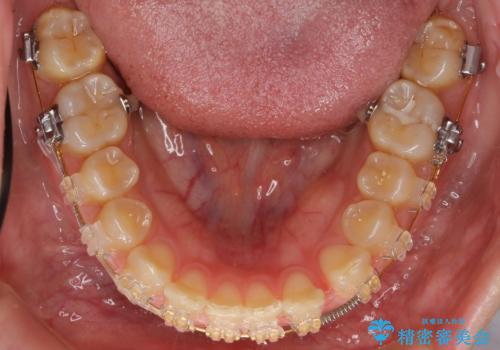

- 審美装置

- 治療期間

- 3年11ヶ月

- 治療回数

- 10-30回